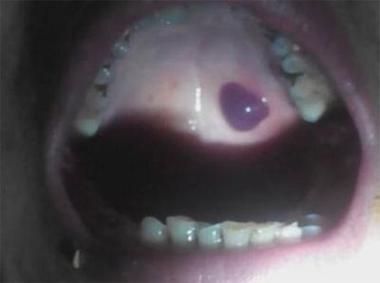

口咽癌

- 这是最严重的后果,口咽癌是指发生在口腔后部、喉咙(咽部)和扁桃体的癌症。

- HPV阳性口咽癌在全球范围内,尤其是在男性中,发病率正在迅速上升,已经成为某些地区(如北美、欧洲)最常见的口咽癌类型,超过了由吸烟和酗酒引起的口咽癌。

- HPV相关的口咽癌通常发生在舌根、扁桃体等部位,其特征是生长相对缓慢,对放化疗比较敏感,预后相对较好(治愈率较高)。